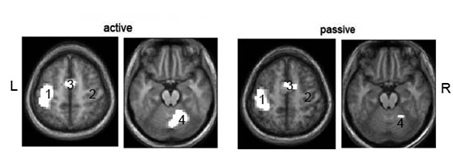

Three of these brain regions are involved in the fMRI response, to both the active and the passive movement of the arm (Figure 1).3,4 The intensity of ВС between the selected points was assessed, as well as the level of their significance.

Figure 1 Averaged fMRI responses of healthy right-handed at the active and passive movement the right hand.3

N17, t=3.69, р<0.001. Digits indicate the selected ROI.